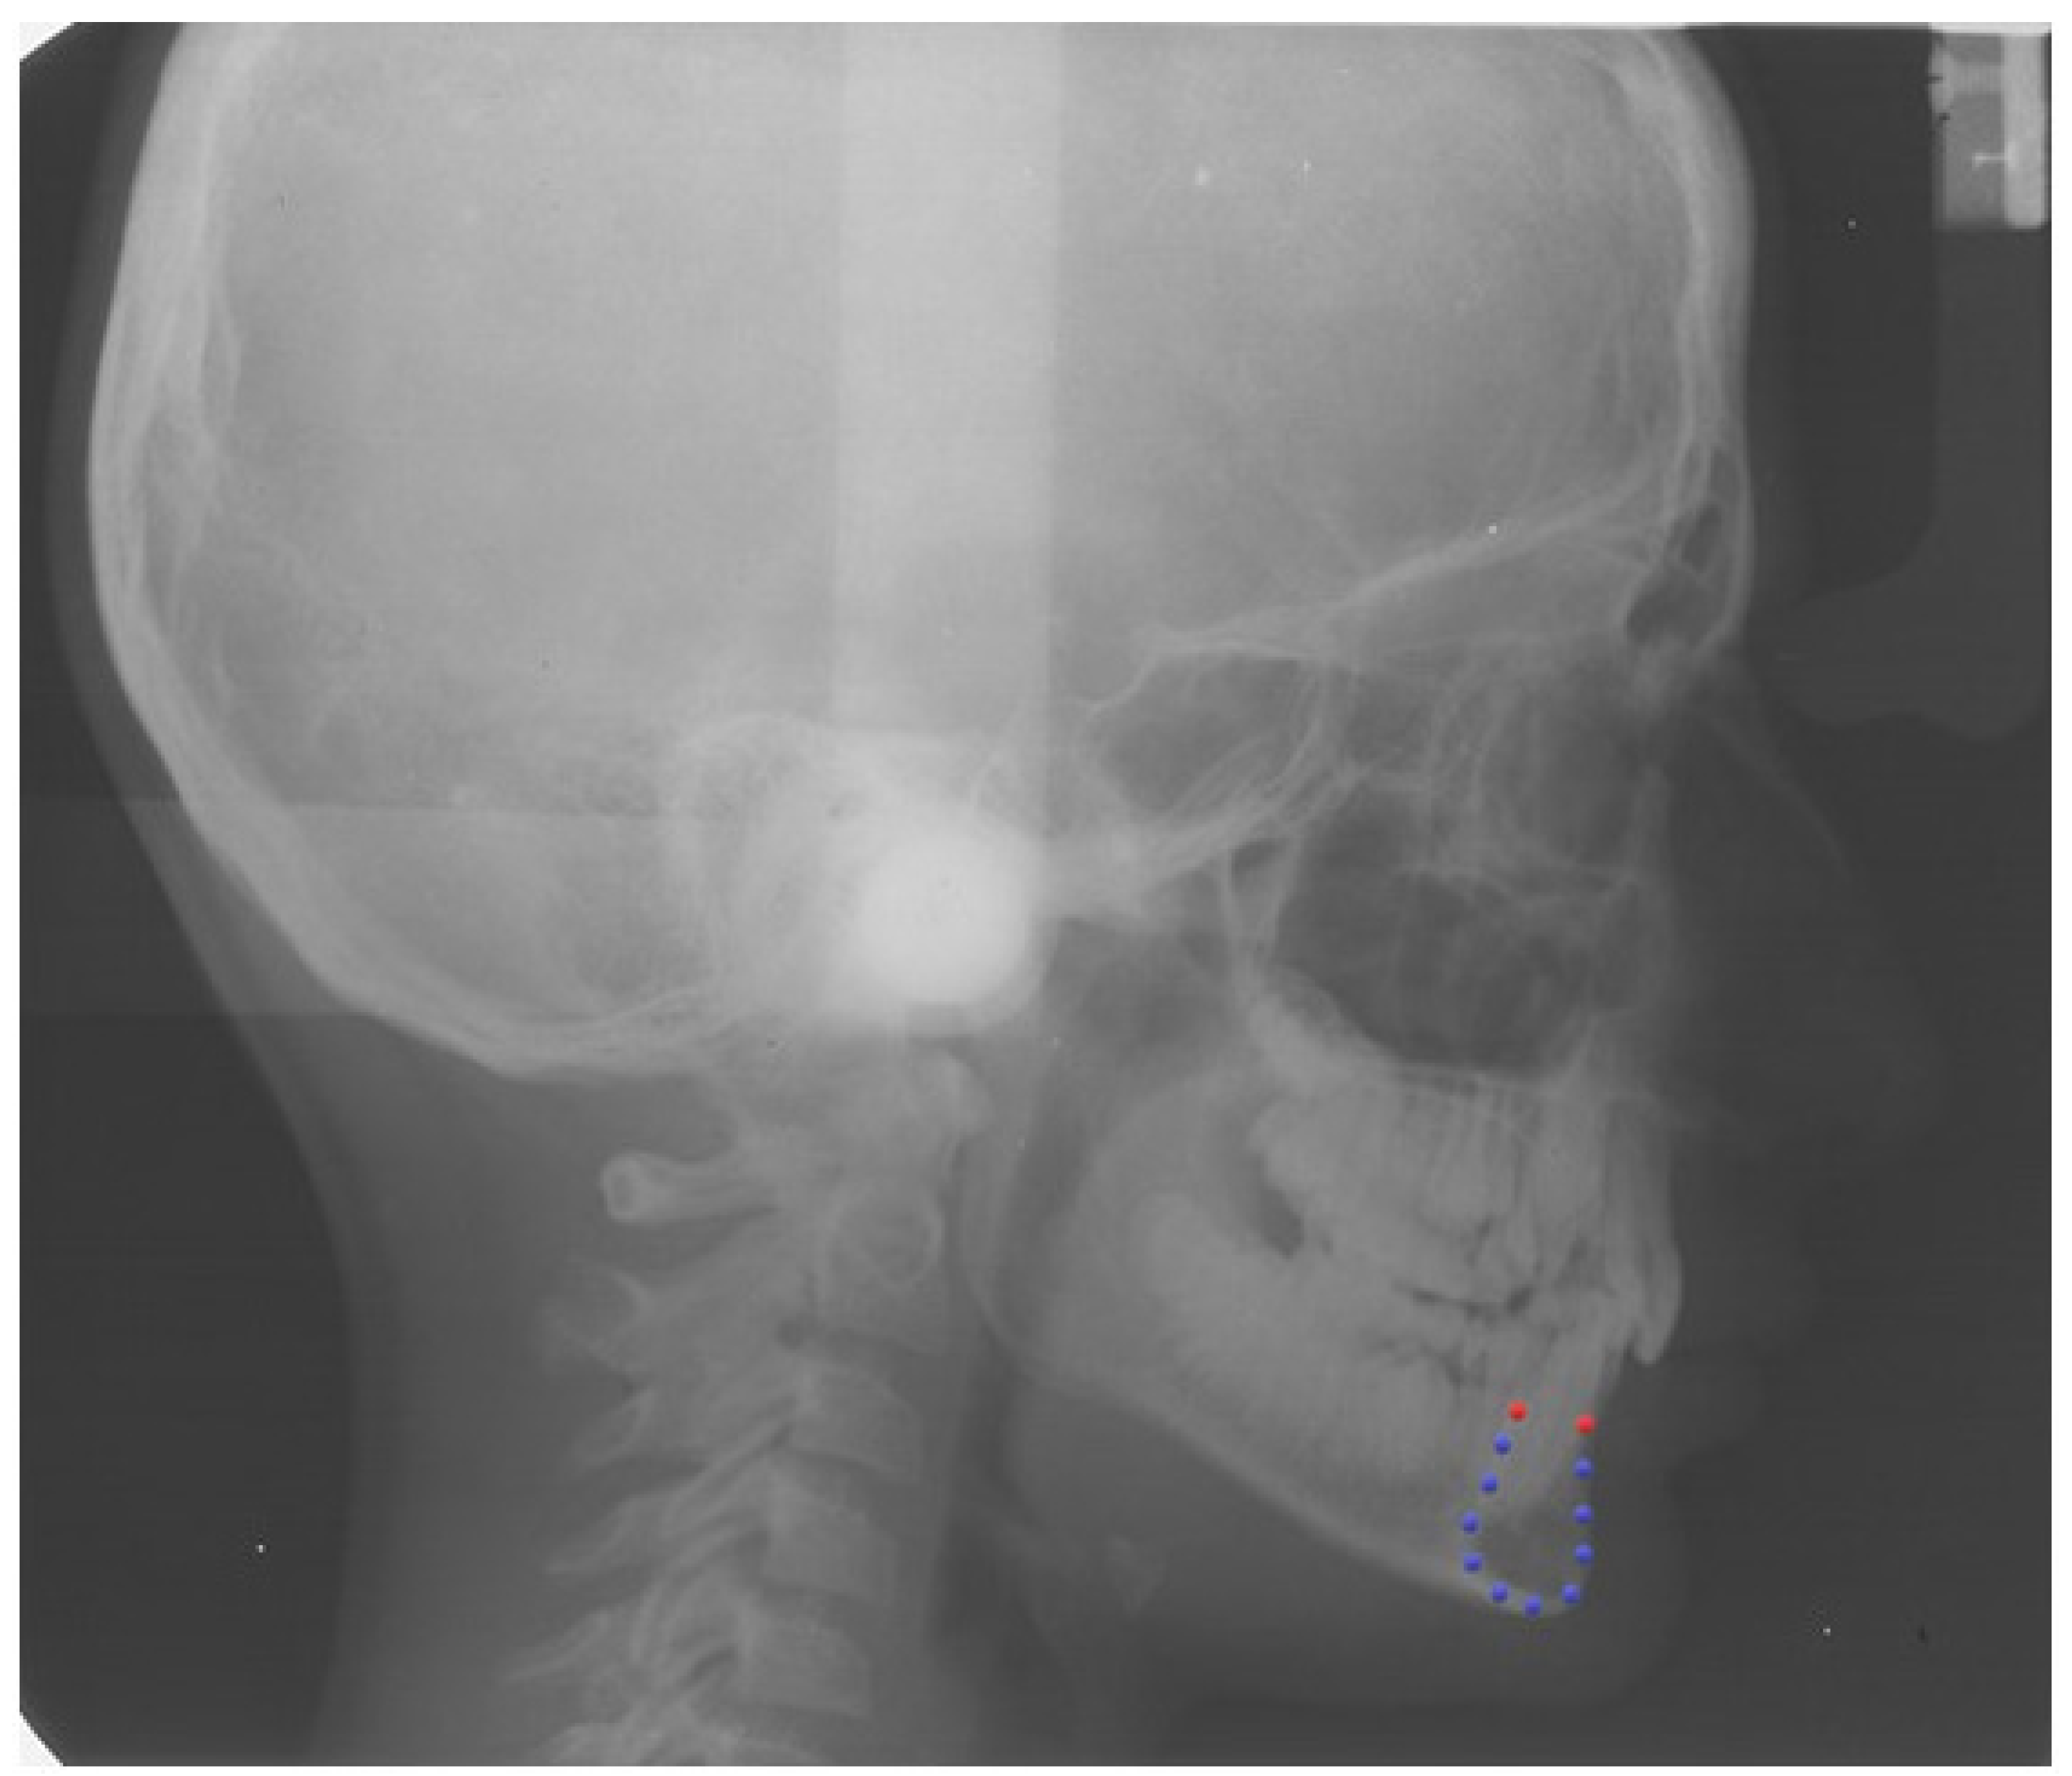

2.2. Definition of the Curve of the Mandibular Symphysis

2.3. Procrustes Superimposition